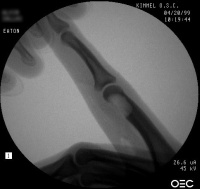

| The tumor was removed with

a burr. |

| Despite extensive

resection, over three quarters of the cortical circumference remained,

and structural reinforcement was not necessary. |

| The defect was packed with

cancellous bone harvested from the dorsal distal radius. |